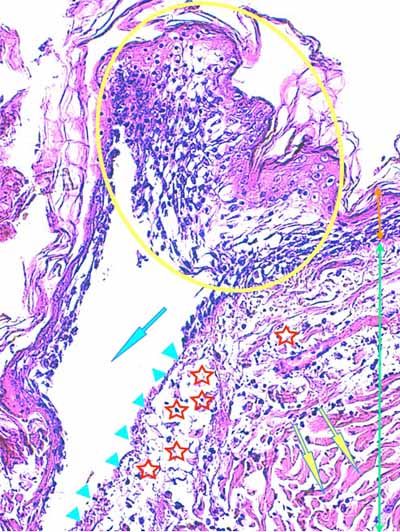

Photo 12 (Hémalun-Eosine X40) : vue rapprochée d’un follicule pileux anormal :

la tige pilaire est fracturée dans son fourreau épithélial lui-même déformé.

Légendes de la Photo 12 :

- Double flèche verte : derme

- Flèche turquoise : tige pilaire fracturée

- Pointe de flèche jaune : canal pilaire

- Triangles turquoises : gaine épithéliale externe du follicule pileux

- Rond bleu : reliquat pigmenté de tige pilaire

Photo 13 (Hémalun-Eosine X200) : dans le derme, on remarque des plages

cellulaires inflammatoires, peuplées de granulocytes neutrophiles,

en étroit rapport avec les unités annxielles folliculo-sébacées.

Légendes de la Photo 13 :

- Étoiles rouges vides : glandes sébacées

- Étoiles rouges pleines : follicules pileux

- Flèches turquoises : plage cellulaire inflammatoire peuplée de cellules pycnotiques et de granulocytes neutrophiles

Photo 14 (Hémalun-Eosine X100) : à la jonction dermo-hypodermique,

un bulbe folliculaire anormal est en rapport direct avec une plage cellulaire inflammatoire.

Légendes de la Photo 14 :

- Étoile rouge vide : adipocyte

- Étoiles rouges pleines : vaisseaux sanguins (une erreur au milieu à droite = adipocyte)

- Pointe de flèche jaune : reliquat de bulbe pilaire fracturé et désolidarisé du reste du follicule pileux

- Flèches turquoises : plage cellulaire inflammatoire peuplée de cellules pycnotiques et de granulocytes neutrophiles, en étroit rapport avec le reliquat de bulbe folliculaire

- Double flèche bleue : hypoderme